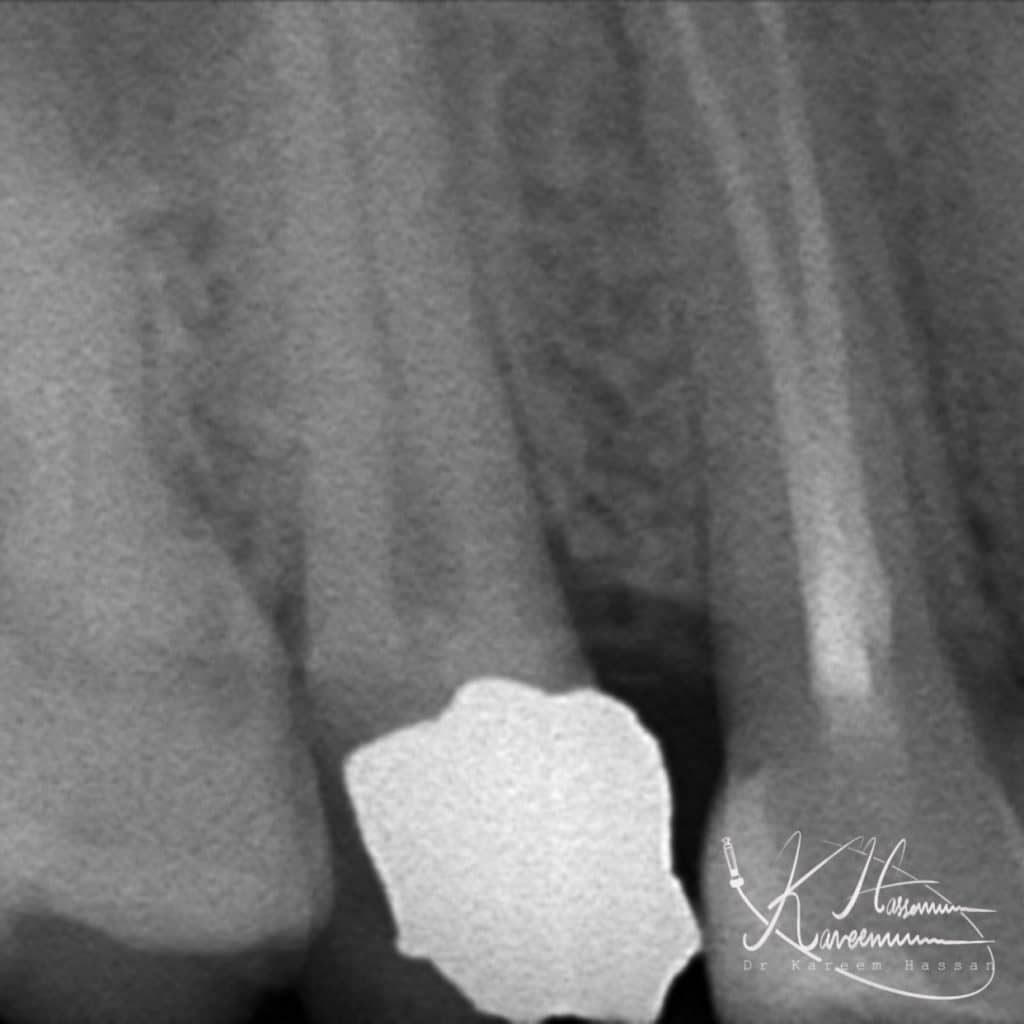

Obturation with bio-c sealer

-RCT with bio-c sealer(one-fill) and hydraulic technique